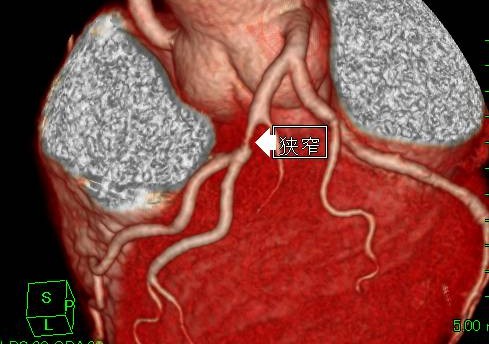

冠動脈CT(冠A-CT)検査について

当院では、冠動脈CT(冠A-CT)検査を行っております。

冠A-CT検査は、心臓の血管(冠動脈)をCTで詳しく調べる検査で、カテーテル検査の前段階として行える、体への負担が比較的少ない検査です。

冠動脈の狭窄(血管の狭くなり)や動脈硬化の状態を画像で確認することができ、自覚症状が出る前の早期の狭心症の発見や、将来の心筋梗塞のリスク評価(予知)に役立ちます。

画像検査

X線CT装置で心臓を画像化するという試みは以前からありましたが、検査のためには息止め時間が最短でも40秒と非常に長く、患者さんに大きな負担を与えてきました。導入されているCT装置は、世界で初めて心臓の検査(120mmのスキャン範囲)を8秒の息止め時間で可能にした装置ですので患者さんの負担を大幅に軽減することが可能です。また立体像(3次元画像)として撮影部を360度自由な方向から観察することが可能です。

このX線CTを使用することにより、従来の画像診断装置では困難であった無症状の心血管の狭窄(きょうさく:せまくなっている)を早期に発見したり、カテーテル治療(細い管を体内に挿入し、その先端を風船状に膨らませて心血管の狭窄部分を広げたりする治療)のフォローアップ検査装置として期待されています。